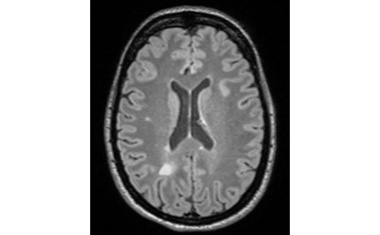

ETH-Forschende haben ein neues Verfahren der Magnetresonanztomographie (MRT) entwickelt mit dem Multiple Sklerose (MS) frühzeitig erkannt und besser überwacht werden kann.

Die Messung des Myelinwasseranteils in Kombination mit biophysikalischer Modellierung stellt einen entscheidenden Fortschritt in der MS-Diagnostik dar.